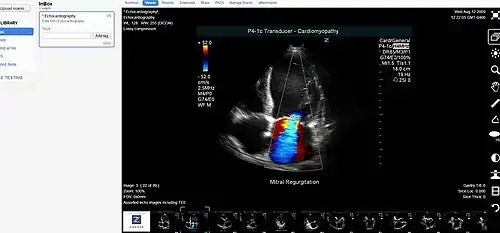

Medical image sharing is the electronic exchange of medical images between hospitals, physicians and patients. Rather than using traditional media, such as a CD or DVD, and either shipping it out or having patients carry it with them, technology now allows for the sharing of these images using the cloud. The primary format for images is DICOM (Digital Imaging and Communications in Medicine). Typically, non-image data such as reports may be attached in standard formats like PDF (Portable Document Format) during the sending process. Additionally, there are standards in the industry, such as IHE Cross Enterprise Document Sharing for Imaging (XDS-I), for managing the sharing of documents between healthcare enterprises. A typical architecture involved in setup is a locally installed server, which sits behind the firewall, allowing secure transmissions with outside facilities. In 2009, the Radiological Society of North America launched the "Image Share" project, with the goal of giving patients control of their imaging histories (reports and images) by allowing them to manage these records as they would online banking or shopping.[1]

- DICOM - A standard for handling, storing, printing, and transmitting information in medical imaging.